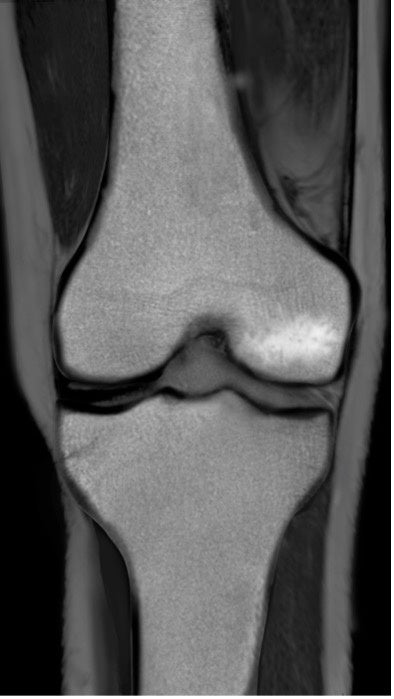

BML(Bone marrow lesion、骨髄異常陰影)はMRIで発見することのできる骨髄内の異常のことを言い、軟骨の下の骨の微小骨折による骨髄内の炎症または浮腫(水分が骨に溜まった状態)、壊死(骨が死んでしまった状態)をあらわすとされています。

BMLは痛みと強い関係があることが示されていて、標準的な保存治療のヒアルロン酸注射や近年注目されている再生医療のPRP療法でも改善しない関節痛の原因となっている可能性が指摘されています。